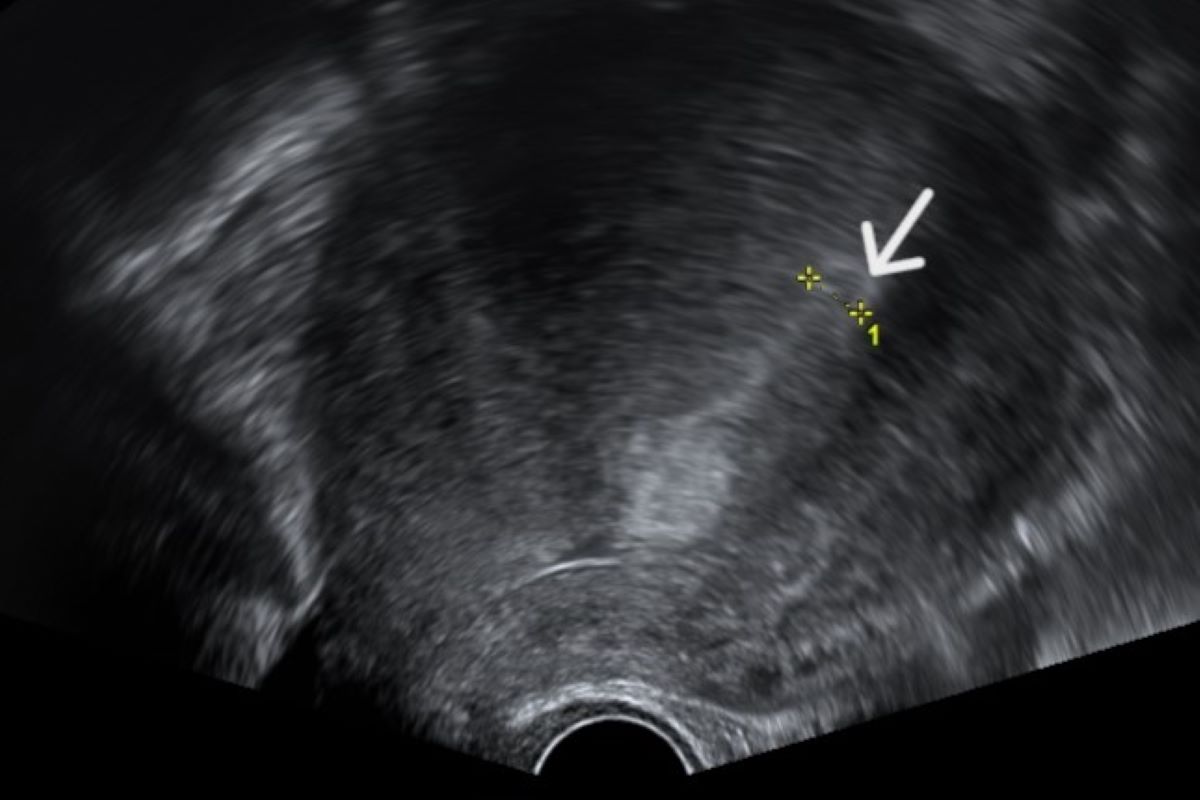

60歲的吳女士因停經後仍不定期出血,定期在的門診追蹤檢查。在某次回診中,醫師透過超音波檢查發現了吳女士的子宮內膜厚度異常增生,遂決定替她進行「子宮內膜搔刮術」,做進一步採樣。醫師於術中發現吳女士的子宮中有一塊肉瘤,若不及時處理,很有可能病變為「子宮內膜癌」。因此,雙方討論後,決定以摘除子宮的方式以根除病灶。

由於缺乏類似子宮頸抹片的普及篩檢方法,子宮內膜癌的診斷較為困難,目前多使用「子宮內膜抽吸術」或是「子宮內膜搔刮術」進行子宮內膜的採樣,並將檢體送至病理化驗,再進一步評估。

「子宮內膜抽吸術」是可以於門診進行的簡單方式,在不用麻醉的情形下,醫師會將一支細管從受檢者的陰道進入,並經由子宮頸進入子宮內,抽取少量子宮內膜組織;而「內膜搔刮術」則須於手術室中進行,在受檢者全身麻醉或是局部麻醉的狀態下,醫師會使用器具將子宮頸擴張至適當寬度,再將刮匙伸入子宮內刮取內膜組織,相較之下採集的範圍會較全面。

臨床上會依據內膜增生情況、病灶嚴重程度及病人臨床狀況如體力等決定採樣方式。若經過病理檢驗確定為內膜癌,治療則主要會以手術為主,輔以放射治療、化療及標靶治療等方式移除病灶。該病早期五年存活率可高達90%,晚期則大幅減半至30%以下,因此及早發現可以及早治療。